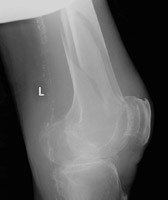

- Click on the image for a larger versionBLateral radiograph of the distal femur.